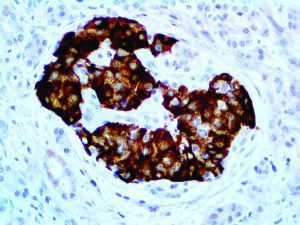

It is the ICU physician who is most likely to witness one of the deadliest manifestations of the abnormal immunological response, the cytokine storm syndrome (CSS). This response is also referred to by some as the cytokine release syndrome (CRS). CSS is characterized by continuous activation and expansion of macrophage and lymphocyte populations, which secrete large amounts of cytokines, causing the cytokine storm. This massive cytokine release is akin to hemophagocytic lymphohistiocytosis (HLH) disease, a syndrome characterized by initial unchecked and persistent activation of cytotoxic T lymphocytes and NK cells.

Clinical and laboratory manifestations of HLH include fever, enlarged liver and/or spleen, neurologic dysfunction, coagulopathy, liver dysfunction, cytopenias (i.e., low levels of erythrocytes, leukocytes, and/or platelets), hypertriglyceridemia, hyperferritinemia, hemophagocytosis, and eventually diminished NK cell activity as the immune system becomes progressively paralyzed. HLH can be familial (primary HLH) or secondary to another disease process (sHLH), such as rheumatic disease, in which it is referred to as macrophage activation syndrome (MAS, characterized by elevated ferritin).